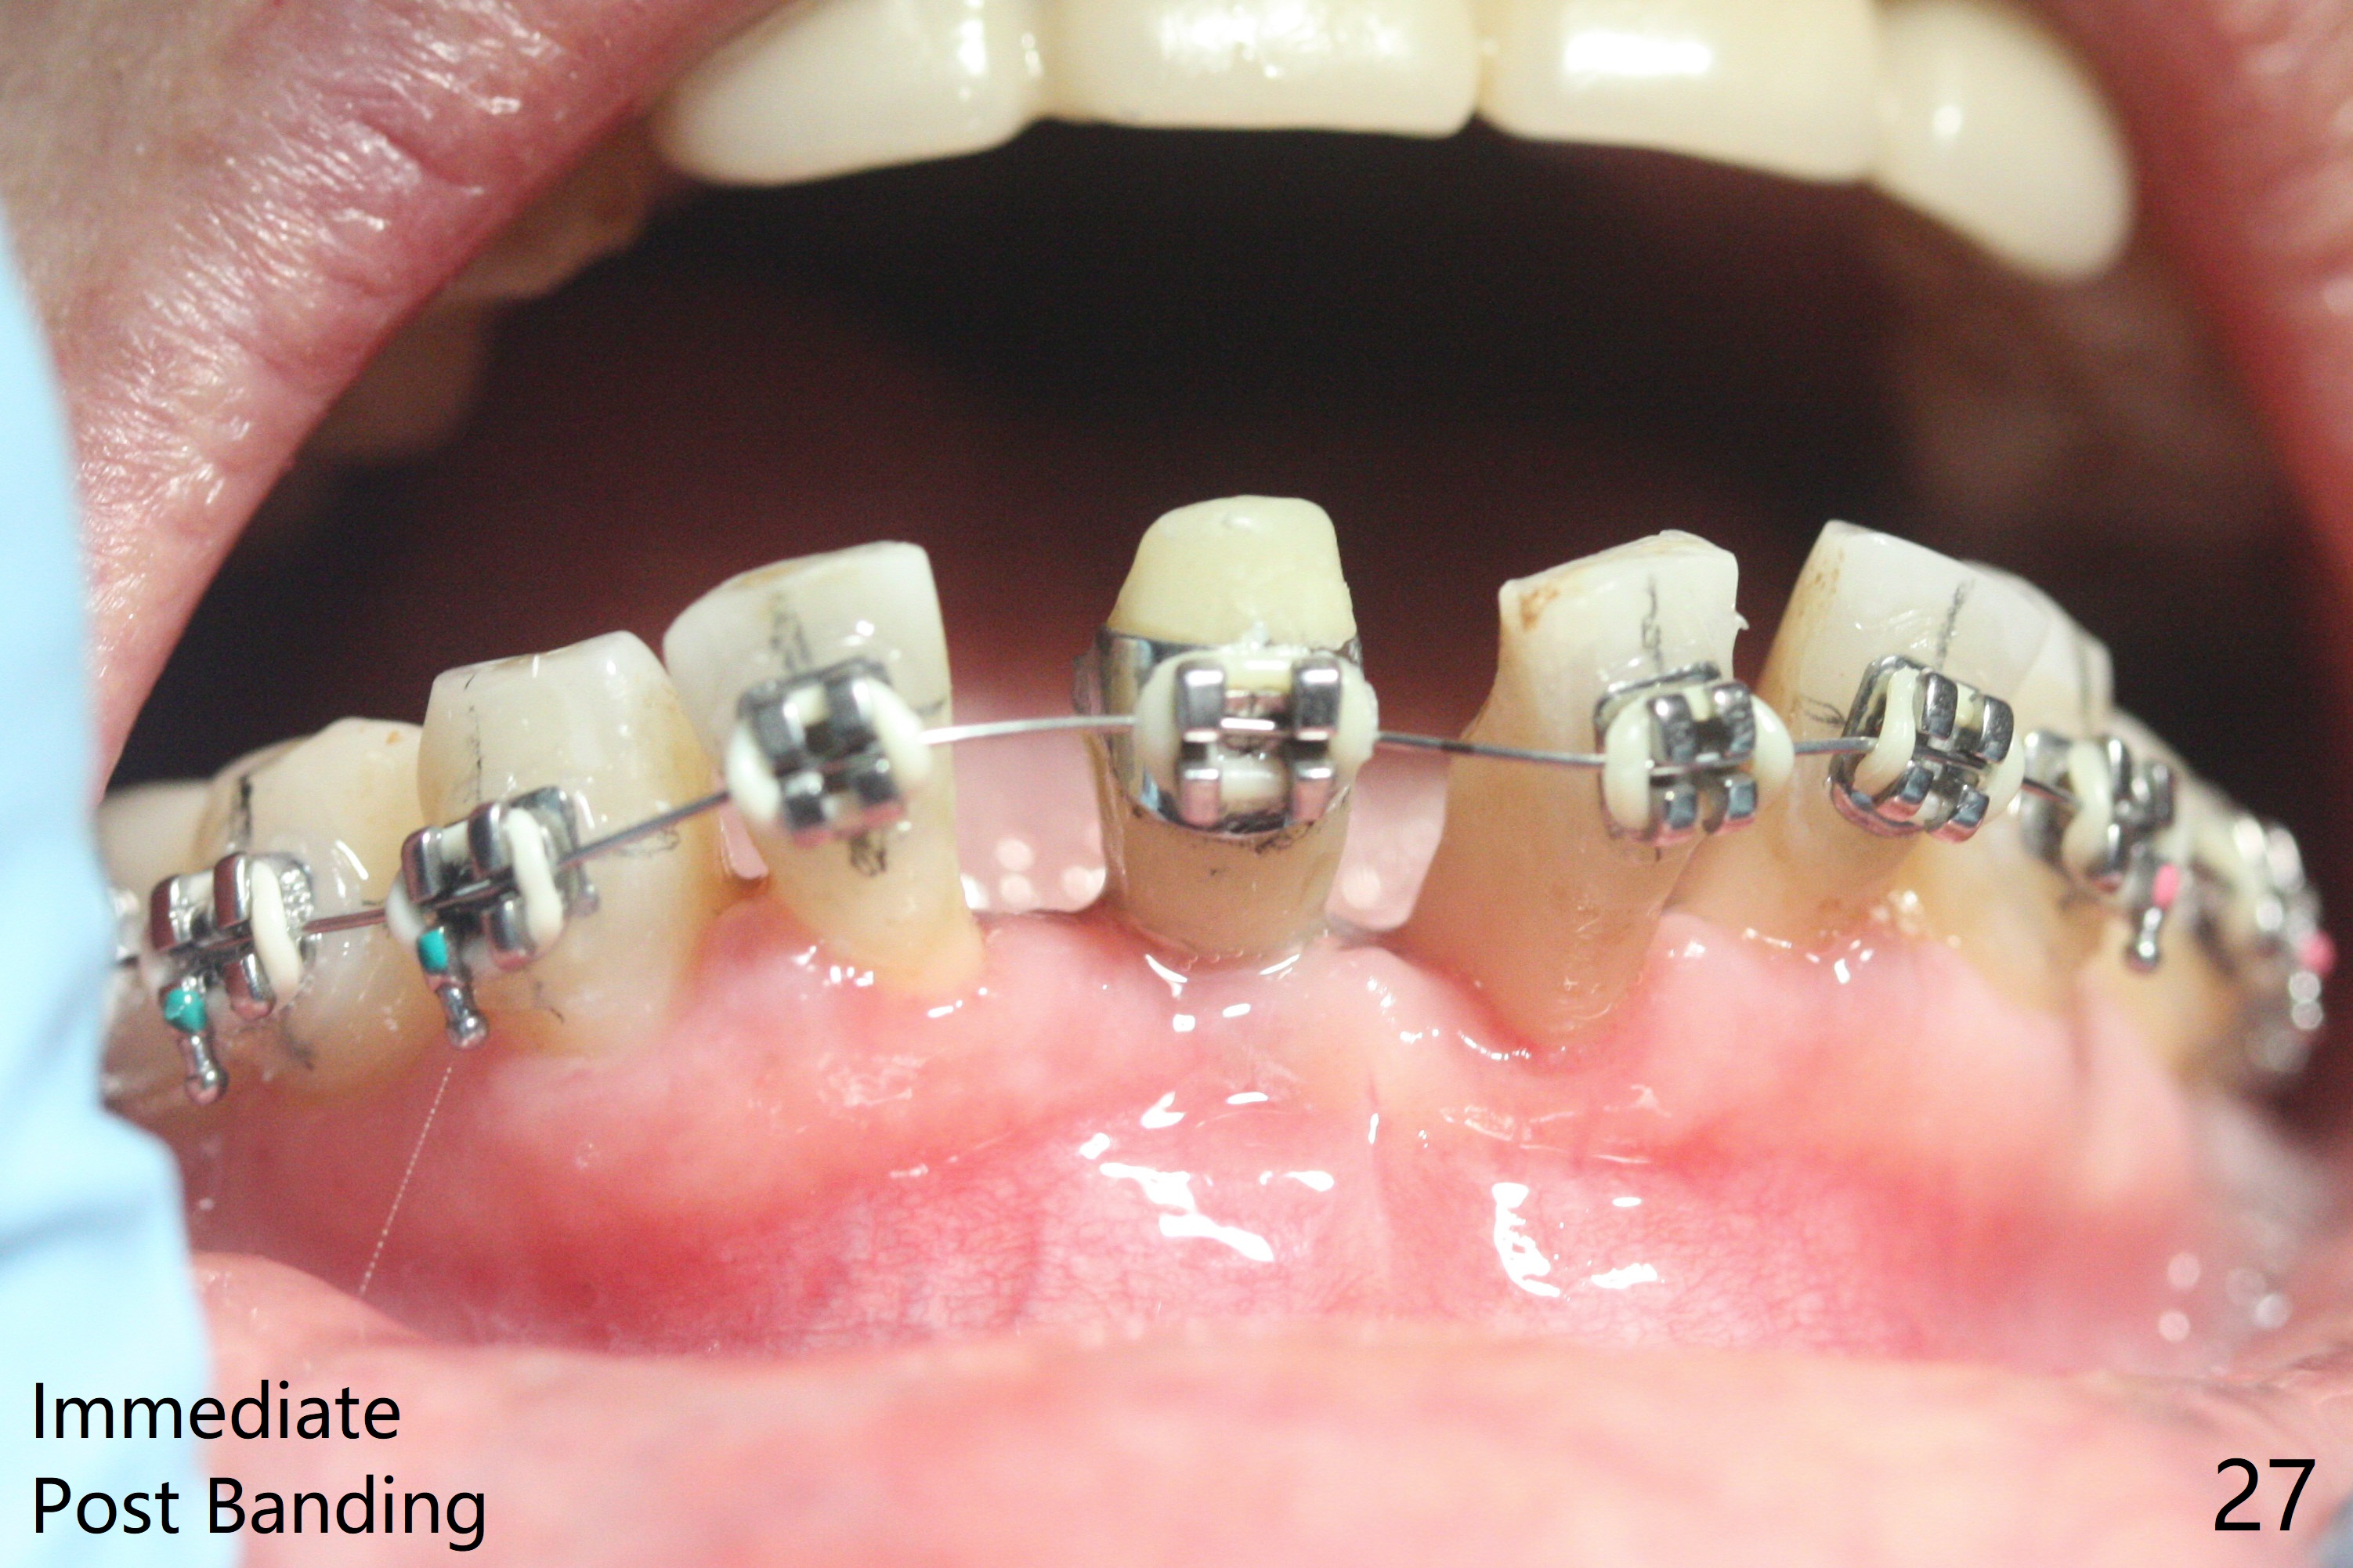

56岁女十分恐惧治疗,缺失右下1,其余切牙由于骨质吸收颊侧移位(图一:1,2),但是她不愿意拔除,同意右下1种植,牙周骨手术,植骨;植体整合后作为支抗,矫正移位下门牙。为了防止忘记舌侧瓣分离,先做舌侧切口(图二),然后颊侧瓣松弛分离(图三),包括使用前牙隧道刀(图四)切断颊侧骨膜,松弛到颊侧瓣能向舌侧牵拉3-4毫米(图五),舌侧瓣骨膜下广泛,深部分离(好像不能切断骨膜,图六),放置导板,磨平狭窄的牙槽嵴(图七:O(osteotomy)),植入2.5x12(4)毫米一段式植体(图八:故意舌侧植入,以便以后矫正),在颊侧骨板打多个出血洞(图八:箭头),然后把在平的器皿上形成的粘性骨板(sticky bone,图九),放置于植体和移位切牙周围(图十),接着使用消毒过的橡皮障punch(图十一(纸头相当于PRF膜;事先给助手示范))在三个PRF膜(图十二)打洞,套在植体和门牙上(图十三: 箭头),防止膜(图十四)和骨块(图十五,十六:*)移位,最后还必须使用最原始方法牙周敷料保护伤口(图十七)。术后9天,舌侧牙周敷料脱落,伤口稍微裂开(图十八)。术后18天撤除敷料,伤口裂开处有新鲜肉芽组织生长(图十九(*:下面是填入的骨粉,将是增宽的牙槽嵴(如果你是乐观主义者)),二十)。病人十分感激我们帮助她度过难关。她的确有sleep apnea,否定tongue thrust。术后三个月植体周围没有明显骨质吸收(图二十一至二十三),左下1,2轻度反合(图二十四),植体周围软组织健康(图二十五),5-5安置矫正器(图二十六,二十七,12 niti)。一周后下切牙向舌侧移动(图二十八),左下1,2反合纠正(图二十九)。再一周变化不大(图三十),植牙圈有些松动,两周后将重做临时牙冠,槽往舌侧移动。结果病人提前回来,植牙槽舌侧移位。一周后右下2不适(图三十一),尝试近中牵引(图三十二)。